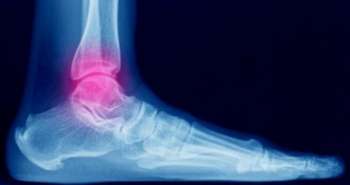

These days’ nanotechnology‐based medicines, the nanomedicines (NMs) have gained attention as an effective treatment strategy to counter health issues like arthritis. Pre‐clinical research scientists, as well as physicians from all over the globe, support this approach. Therefore, Lu Liu and colleagues found out the targeted stimuli‐responsive NMs as a rheumatoid arthritis (RA) treatment approach in the last five years. Various milestones have been achieved in the clinical treatment of RA, but these therapies present certain shortcomings which begin from the adaptive treatment tolerance (ATT) following the long‐term drug use which leads to reduced efficacy, increasing sustained drug dose and critical adverse events. There is a need to establish innovative therapeutic approaches to overcome these challenges.

The nanotechnology‐based nanomedicines (NMs) are emerging as treatment for RA. One of the fundamental concepts in building more convenient multifunctional NMs formulations for efficient RA treatment is its targeted stimuli‐responsive features. Because of NMs delivery and on‐demand liberation of medicaments at targets in response to internal or external stimuli associated with the RA pathophysiology helps to postpone the RA progression efficiently and with no side effects on healthy tissues.